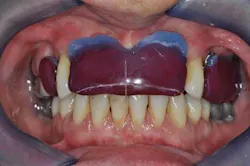

Figs. 6 a, b, c, and d: RPD framework try-in, bite record with mandibular implant-supported metal frameworks and mounting

- Try-in and final bite registration.

- Final mounting.

Figs. 7a, b, and c: Teeth and ceramic mounting